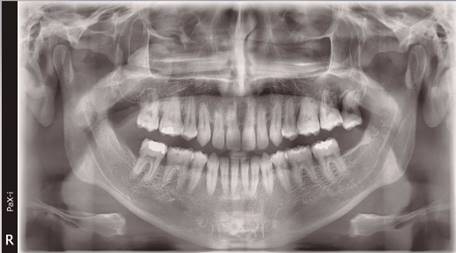

Se reporta el caso de un paciente de sexo masculino, 34 años, sin enfermedades sistémicas conocidas al momento de la primera consulta. No consume medicamentos, no es fumador. Acude en Julio de 2018 derivado por especialista en rehabilitación oral al especialista en periodoncia en la Clínica Odontológica CODUC de la UC. El paciente aceptó la publicación de este caso clínico a través de la firma de un documento de consentimiento informado institucional. El paciente manifestaba un aumento de volumen de la encía de características inflamatorias que comprometía encía marginal, adherida y papilas y que cubría tres cuartos de la corona clínica desde el diente 4.4 al 3.3 (Figura 1). A nivel radiográfico no se observaron efectos de la lesión gingival sobre el tejido óseo ni dientes comprometidos (Figura 2). Al examen clínico el tejido gingival presentaba sangramiento al sondaje sin sintomatología dolorosa asociada. A nivel periodontal se detectó pérdida de inserción periodontal de 1 a 3 mm en el sector de molares. La profundidad al sondaje varió entre 2 y 3 mm. Dada la gravedad de la enfermedad y sospecha de lesión neoplásica no se realizó un registro detallado de nivel de inserción ni profundidad al sondaje de todos los sitios periodontales. Debido a las características clínicas y ubicación de la lesión, la hipótesis diagnóstica pre-quirúrgica planteada fue de un fibroma odontogénico periférico. Dado el alto compromiso inflamatorio y sangramiento asociado, se le indicó al paciente Amoxicilina 1 gramo asociado a Metronidazol 500 miligramos, cada 12 horas durante 7 días con el propósito de reducir la inflamación e infección antes de la cirugía. Luego de dos semanas la lesión no cambió en sus aspectos inflamatorios. Como tratamiento, se decidió la eliminación quirúrgica de la lesión y su análisis mediante histopatología. El examen histopatológico mostró una lesión inflamatoria con gran infiltración por polimorfo nucleares neutrófilos, células gigantes multinucleadas y vasos sanguíneos dilatados asociados a hemorragia (Figura 3). Se solicitó una evaluación de la bioquímica sanguínea, la cual no entregó alteraciones compatibles con neoplasia maligna. El examen histopatológico se realizó en paralelo con el estudio de lesiones inflamatorias que estaban presentes en las fosas nasales por un especialista otorrinolaringólogo, quien detectó pólipos nasales. El paciente finalmente se derivó a un especialista en reumatología quien realizó el diagnóstico definitivo de Granulomatosis de Wegener (GPA) luego del examen clínico y determinación del examen ANCA a nivel sanguíneo. El paciente fue tratado con metotrexato y corticoesteroides. Luego de 2 años el paciente se encuentra sano, sin manifestaciones del Wegener en los tejidos periodontales (Figura 4).